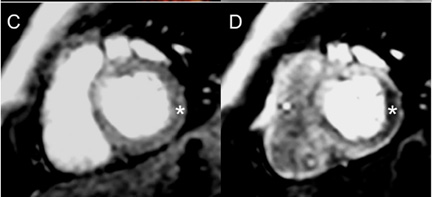

Stress Testing

Description: A stress test is done to check the blood supply to the heart at rest and under stress. This is usually done for coronary problems either before or after surgery. During a stress test, a medication is given through an IV to increase the heart rate.

Why MRI: The increased heart rate from the IV medication is like exercise. Heart MRI can detect normal and abnormal flows in the blood supply to the heart during a stress test. This can help your doctor decide if treatments such as surgery may be needed.

Images: Stress imaging